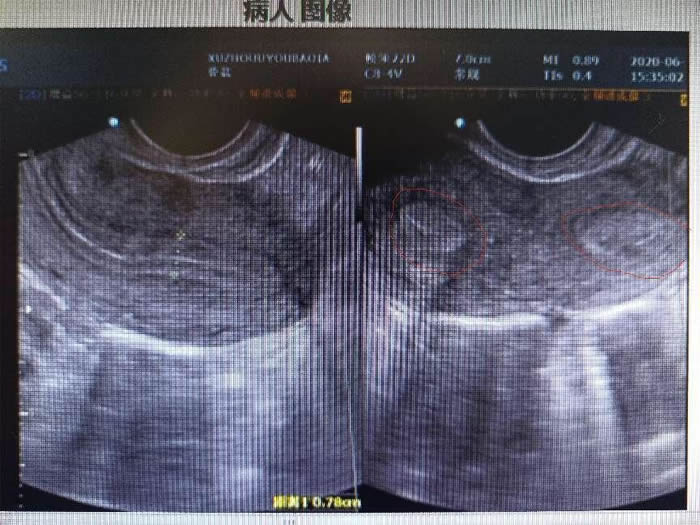

一年前,陳女士因?yàn)榻Y(jié)婚兩年未孕、痛經(jīng)嚴(yán)重來到徐州市婦幼保健醫(yī)院就診。彩超檢查后發(fā)現(xiàn)陳女士子宮畸形,單角子宮合并殘角子宮II型,殘角子宮有功能內(nèi)膜,與單角子宮宮腔不相通,每次月經(jīng)經(jīng)血逆流導(dǎo)致陳女士腹痛難忍,日常還伴有同房的性交痛。

考慮到陳女士很年輕有強(qiáng)烈的生育愿望,李桂林教授團(tuán)隊(duì)制定了腹腔鏡下右側(cè)殘角子宮加右側(cè)輸卵管切除的手術(shù)方案。手術(shù)過程比想象還復(fù)雜,術(shù)中發(fā)現(xiàn)陳女士盆腔重度粘連,右側(cè)殘角子宮合并腺肌癥、左側(cè)卵巢巧克力囊腫,左側(cè)輸卵管粘連積膿,不可逆損傷。李桂林教授與團(tuán)隊(duì)成員立即調(diào)整手術(shù)方案,為了最大程度保留她的生育能力,臨時決定將本來要切除的右側(cè)殘角子宮連接的輸卵管“嫁接”到單角子宮的右側(cè)。